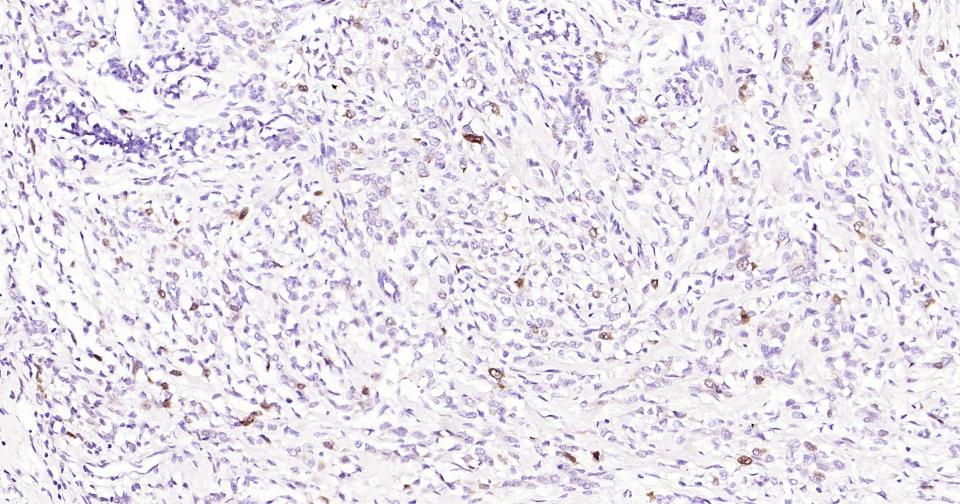

Paraformaldehyde-fixed, paraffin embedded Human Gastric Cancer; Antigen retrieval by boiling in sodium citrate buffer (pH6.0) for 15 min; Antibody incubation with Phospho-CDK1/2 (Thr14) Monoclonal Antibody, Unconjugated(bsm-61198R) at 1:200 overnight at 4°C, followed by conjugation to the SP Kit (Rabbit, SP-0023) and DAB (C-0010) staining.

Paraformaldehyde-fixed, paraffin embedded Human Breast Cancer; Antigen retrieval by boiling in sodium citrate buffer (pH6.0) for 15 min; Antibody incubation with Phospho-CDK1/2 (Thr14) Monoclonal Antibody, Unconjugated(bsm-61198R) at 1:200 overnight at 4°C, followed by conjugation to the SP Kit (Rabbit, SP-0023) and DAB (C-0010) staining.

Paraformaldehyde-fixed, paraffin embedded Human Colon Cancer; Antigen retrieval by boiling in sodium citrate buffer (pH6.0) for 15 min; Antibody incubation with Phospho-CDK1/2 (Thr14) Monoclonal Antibody, Unconjugated(bsm-61198R) at 1:200 overnight at 4°C, followed by conjugation to the SP Kit (Rabbit, SP-0023) and DAB (C-0010) staining.

Paraformaldehyde-fixed, paraffin embedded Human Prostate Tumor; Antigen retrieval by boiling in sodium citrate buffer (pH6.0) for 15 min; Antibody incubation with Phospho-CDK1/2 (Thr14) Monoclonal Antibody, Unconjugated(bsm-61198R) at 1:200 overnight at 4°C, followed by conjugation to the SP Kit (Rabbit, SP-0023) and DAB (C-0010) staining.

Paraformaldehyde-fixed, paraffin embedded Human Esophagus Cancer; Antigen retrieval by boiling in sodium citrate buffer (pH6.0) for 15 min; Antibody incubation with Phospho-CDK1/2 (Thr14) Monoclonal Antibody, Unconjugated(bsm-61198R) at 1:200 overnight at 4°C, followed by conjugation to the SP Kit (Rabbit, SP-0023) and DAB (C-0010) staining.

Paraformaldehyde-fixed, paraffin embedded Human Liver Cancer; Antigen retrieval by boiling in sodium citrate buffer (pH6.0) for 15 min; Antibody incubation with Phospho-CDK1/2 (Thr14) Monoclonal Antibody, Unconjugated(bsm-61198R) at 1:200 overnight at 4°C, followed by conjugation to the SP Kit (Rabbit, SP-0023) and DAB (C-0010) staining.